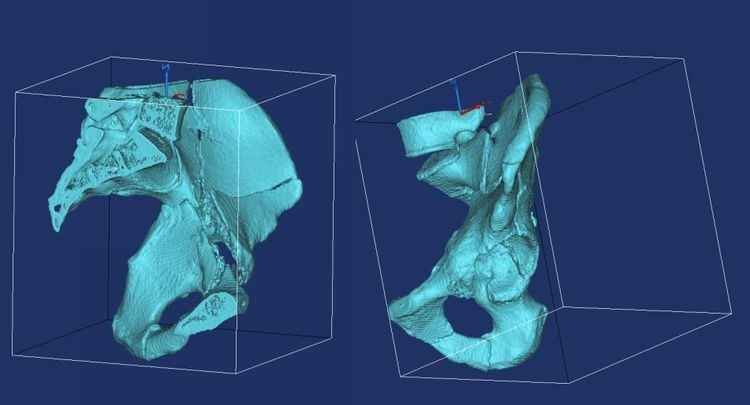

利用mimics重建三维